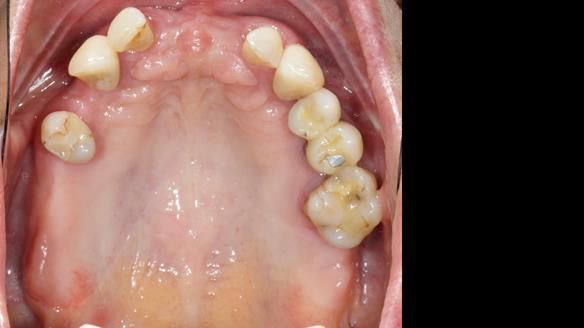

She had previously suffered from generalised periodontitis – stage IV, grade C, currently stable, with reduced attachment across the upper arch.

By the time she came to me, her periodontal condition was stable — but the aesthetics in the upper jaw were very poor.

We provided her with an immediate upper denture (Mk 1), followed by a definitive metal-based upper denture (Mk 2). A lower removable partial denture was discussed, to be made only if needed once the upper treatment was complete. However, at review, this wasn’t necessary — Adnana had excellent neuromuscular control and function, even with a shortened dental arch (SDA).